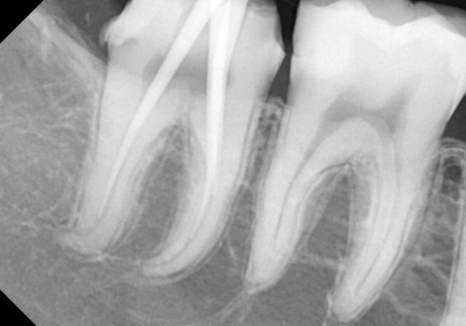

하지만 엑스레이를 찍어보니

상황이 조금 달랐습니다.

사랑니가 앞 치아(#47) 쪽으로

비스듬히 누워 있는 상태였거든요.

그동안 사랑니에 가려져 보이지 않던

앞 치아의 뒷면이 새까맣게 썩어 있었거든요.

사랑니가 찰싹 붙어있던 자리에

음식물 찌꺼기들이 쌓이면서,

앞 치아의 옆구리가 야금야금 썩어 들어간 거죠.